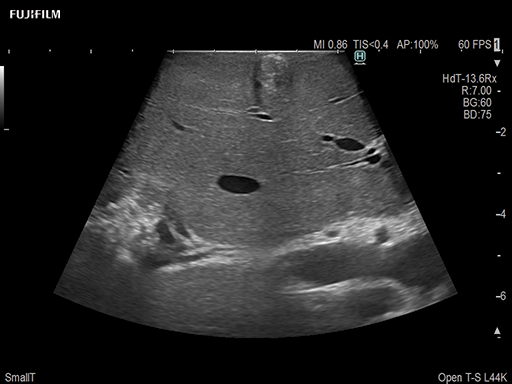

Liver Ablation Procedure using L44K

Linear array side-fire “T” transducer for open surgical procedures, providing exceptional near and far-field resolution.